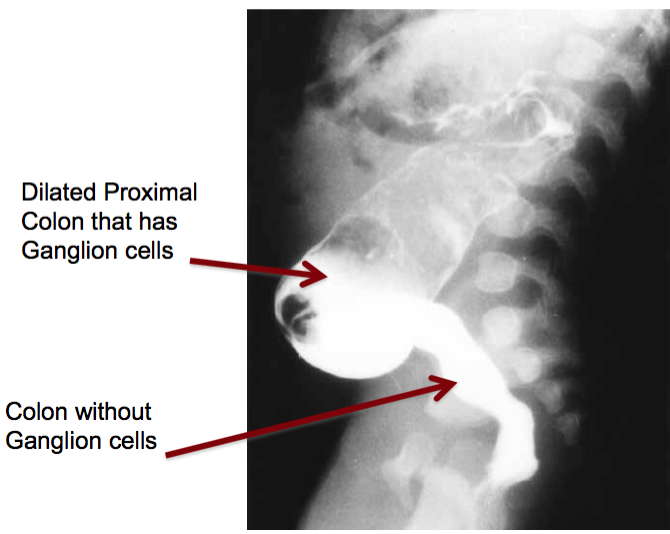

What is Hirschsprung disease and how dose it present?

Failure of neural crest migration -> absence of nerve plexi in the distal colon -> poo gets backed up and infants present with megacolon.